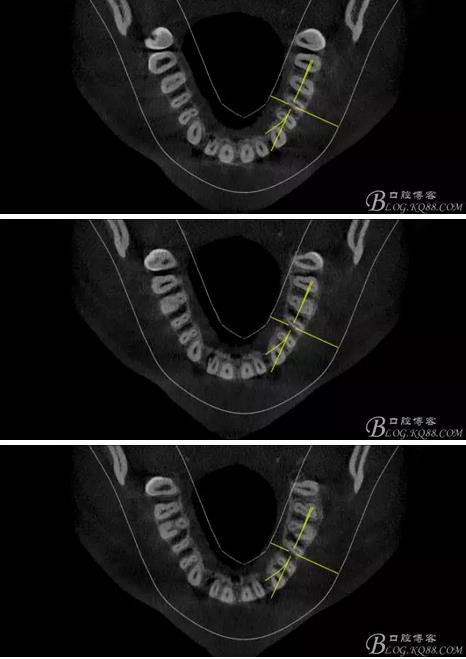

(1) 檢查:12唇側(cè)牙齦可見竇道,牙體顏色較鄰牙暗,無光澤,形態(tài)完整無缺損,唇側(cè)及近遠中向未提及牙周袋。腭側(cè)齦緣輕度紅腫,舌側(cè)窩可探及裂溝,可見浸墨狀痕跡,沿裂溝舌側(cè)探診牙周袋深大于11mm,除患牙外全口牙周狀況良好,為探及牙周袋,牙齦色粉紅。邊緣菲薄,質(zhì)地堅韌。12冷熱診無反應,叩診(+-),無明顯松動,無咬合創(chuàng)傷。12根尖x線片示,根管中三分之一中可見一斜向線樣透射影像根尖區(qū)及遠中根三分之一可見低密度透射暗影,錐形束CT示12根尖區(qū)唇腭向骨吸收已穿通,根面溝達根中三分之一卷曲分出另一牙根,再未見其他明顯的根管系統(tǒng)。

360截圖20170119164928703.jpg

360截圖20170119164942599.jpg

360截圖20170119165027679.jpg

360截圖20170119165037167.jpg